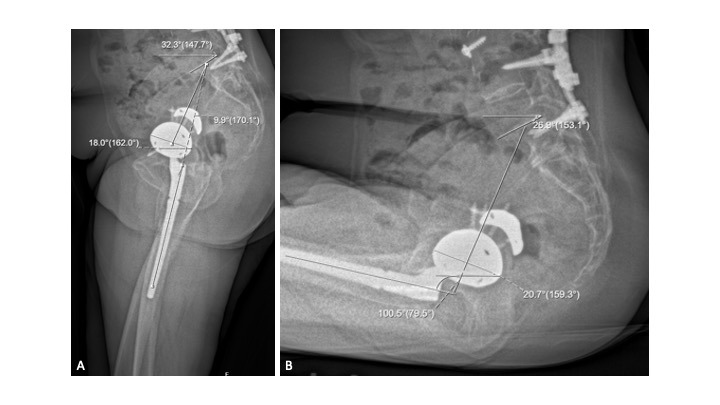

In this case, we surmise that multiple spinal fusions, spanning nearly the entire length of the spine, resulted in significant pelvic hypomobility (standing SS: 32.3°, normal: 38.4° ± 7.2°; and sitting SS 26.9°, normal: 18.5° ± 8.4°) (Ike et al. 2018). Additionally, the pelvic-femoral angle for this patient demonstrates femoral hyperflexion to compensate for diminished pelvic retroversion (standing – 170º, sitting – 100º; normal: 186.8° ± 9.0° and 124.5° ± 12.9°, respectively). As expected for this patient, the increase in ante-inclination is minimal (standing – 18º, sitting – 20.7º; normal: 34.1° ± 8.3° and 53.7° ± 8.8°, respectively), implying a greater risk for anterior impingement and posterior dislocation (Figures 10a-b).